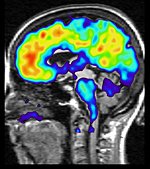

Alzheimers sjukdom är en neurodegenerativ sjukdom som varje år drabbar 20 000-25 000 svenskar. Det är den vanligaste demenssjukdomen och den är dödlig. Forskningen inom området har handlat om nya sätt att ställa tidiga diagnoser och olika metoder för att fördröja sjukdomsförloppet, både med läkemedel och andra behandlingssätt.

Demens är en diagnos för en rad symptom, som exempelvis minnesförlust, koncentrationssvårigheter och nedstämdhet, som kan bero på olika sjukdomar och skador.